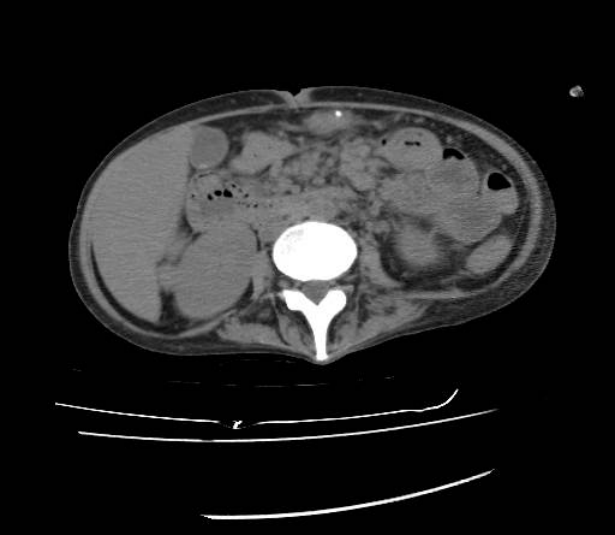

Figure 2.

Abdominal computed tomography (CT) scan revealing ascites, as well as paraaortic and mesenteric lymph node enlargement.